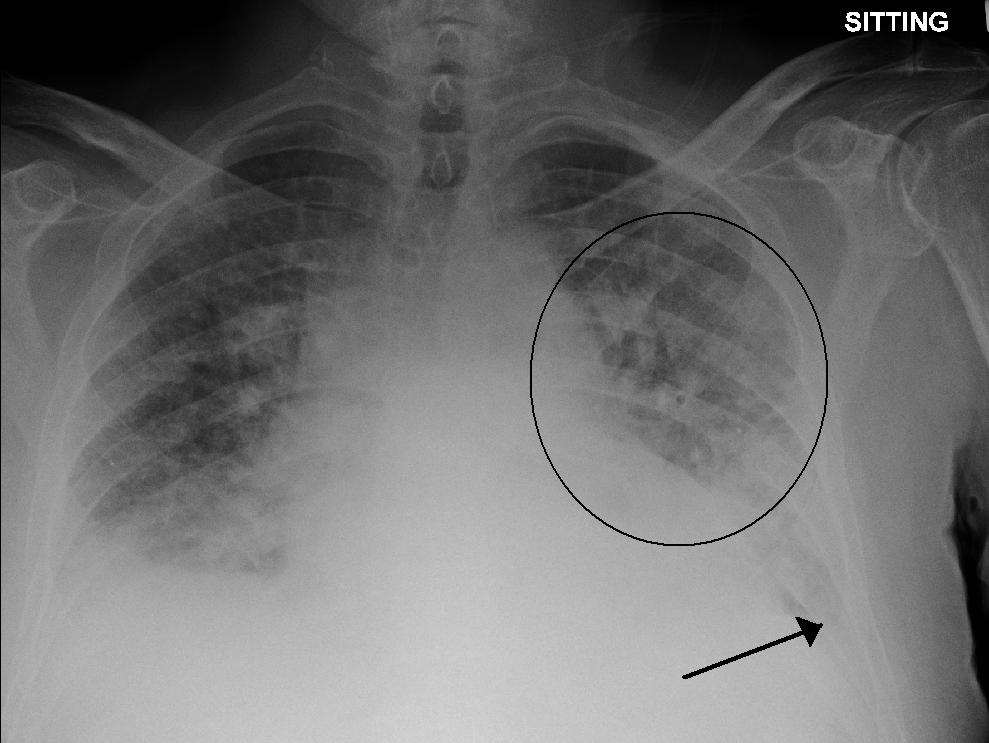

The clinical symptoms from TACO are due to an excess of fluid within the circulatory system. As a result, there is increased pressure within the circulatory system, resulting in fluid moving into the surrounding tissues.[13] In the lungs, the extra fluid accumulates into the air sacs within the lung, causing difficulties in oxygen getting into the blood. This results in low blood oxygen levels and shortness of breath. In the arms and legs, the fluid accumulates in the tissues, causing swelling. This is most prominent in the legs due to the effects of gravity. Conditions that predispose to increased hydrostatic pressure (heart failure and renal insufficiency) or decreased oncotic pressure (liver failure, malnutrition, nephrotic syndrome) places individuals at increased risk for TACO.